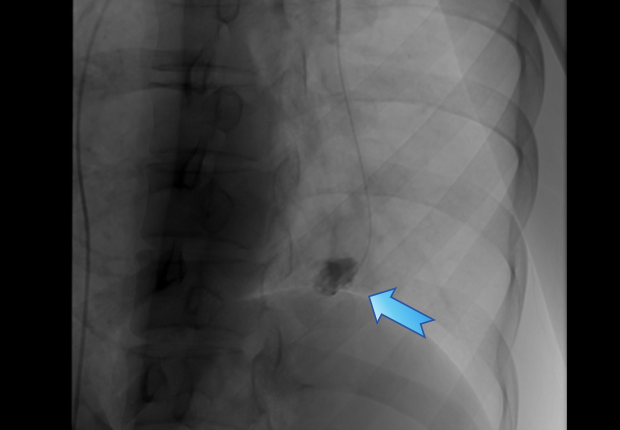

王女士术前CTA图像

王女士很快入住瑞金医院放射介入科病房。经过肺动脉CTA检查后,答案清晰——经团队讨论判定,该病变并非典型“肺内肿块”,而是位于左肺下叶分支血管内的肺动脉动脉瘤。该病变很少见,与咯血高度相关,一旦破裂可导致大出血,性命攸关。